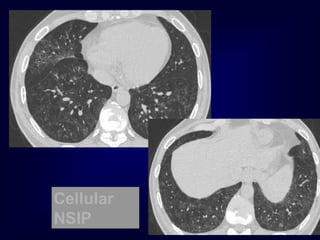

Pathology in white Areas

Alveolitis / Pneumonitis

Ground glass

desquamative intertitial pneumoinia (DIP)

nonspecific interstitial pneumonia (NSIP)

organizing pneumonia

In expiration

both areas (white and black) decrease in

volume and increase in density

DECREASE IN CONTRAST

DIFFERENCES

Cellular

NSIP